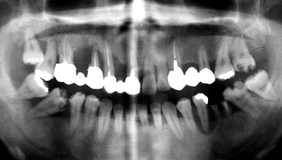

年齢の割にムシ歯が多く、清掃状態も不良。 どうして5│5がないの?

初診時13歳の少年で、Kries 進行傾向が強く3年間の治療期間中に1│5の抜髄を施行。 それ以外にも計7本の保存修復治療を行った。

経過:その後、他院にて治療をしていた様子であるが、13年ぶりに上顎前歯部のKries 治療を 希望して来院。Kries の増加と抜髄処置を受けていることには十分納得出来る相変わらずの清掃状態で であった。

疑問点:20歳前後の10年間で、抜髄しなければならない状況…さらには抜歯に至る状況 にまで至るものでしょうか!!おまけに、6│6の抜髄は惨い!!